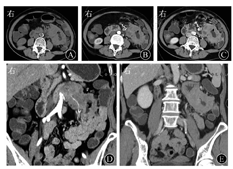

血常规检查显示,RBC计数为3.51×1012/L(下降),平均Hb量为19.4 pg(下降),平均Hb浓度为288 g/L(下降),PLT计数为489×109/L(升高)。尿常规检查阴性。肝肾功能:葡萄糖为8.81 mmol/L(升高),前白蛋白为97 mg/L(下降),白蛋白为32 g/L(下降),肌酐为43 μmol/L(下降),钾离子为3.30 mmol/L(下降)。癌抗原72-4为88.96 kU/L(升高),AFP、CEA、CA125、CA19-9、癌抗原242、癌抗原15-3均阴性。小肠CT检查(图1)显示,左上腹空肠肠壁增厚,最厚处约3 cm,形成软组织肿块伴溃疡形成,病灶密度不均匀,平扫CT平均值为42 Hu,增强后动脉期平均值为65 Hu,门静脉期平均值为75 Hu,局部肠腔扩张,周围肠管结构欠清,周围系膜密度增高,多枚淋巴结影显示部分肿大(最大径>1 cm),呈轻度强化,可见病灶中肠系膜血管呈夹心面包征;直肠壁稍厚。小肠CT检查诊断意见为左上腹空肠占位性病变,首先考虑淋巴瘤,不典型腺癌待排。小肠镜检查(图2)显示至十二指肠中段,乳头下方10 cm处见黏膜隆起增生,触之易出血,肠腔狭窄,小肠镜无法通过,取4块组织行活组织检查。小肠镜检查诊断意见为十二指肠中段隆起增生。

放射科朱乃懿住院医师:病变定位于空肠近段,累及十二指肠水平段。病变的CT表现特点为,肠壁环形明显增厚,累及较长1段肠段,肠腔无明显狭窄,并略扩张,增强后呈渐进性中度强化,肠系膜脂肪密度增高伴多发肿大淋巴结影,与病变肠段一起包绕肠系膜血管类似夹心面包征。其中,①环肠壁明显增厚但肠腔狭窄不明显;②血管包绕;③强化程度;以上3点与典型小肠淋巴瘤的CT表现类似,前两者可为小肠淋巴瘤的相对特征性表现。因此,从小肠CT上诊断首先考虑淋巴瘤,但在极少数情况下,腺癌、间质瘤也会有这样的表现。

结合本病例手术记录中的描述和术后的病理诊断:肿块质地硬,侵犯十二指肠、肠系膜下静脉、结肠脾曲,以及部分肠系膜上动脉侧壁肿大淋巴结。回顾性分析其小肠CT表现特点:①形态上,肿块形态不规则,向内、向外生长,黏膜面凹凸不平,空肠浆膜面呈大小不等的结节状突起,提示病变破坏黏膜,并累及肠道全层。胃肠道NHL的生长方式一般为自黏膜固有层和黏膜下层的淋巴组织沿器官长轴蔓延,再向腔内外侵犯,可以是局部单发和(或)多发结节或肿块,局部黏膜平坦或表面溃疡。本病例肿块沿肠管长轴发展的程度快于沿肠管垂直方向,黏膜面被破坏,与淋巴瘤的表现类似而不易鉴别。肿块周围沿肠系膜浸润导致肠系膜脂肪密度增高,与淋巴结一起包绕血管,类似淋巴瘤的"夹心面包征",这些特点也导致该病例误诊为淋巴瘤。②在强化特点上,本病例呈不均匀环形强化,强化程度要弱于一般肠道腺癌而类似淋巴瘤,尤其是动脉期,肿块强化程度低于周围正常空肠壁,而显得与正常组织有明显分界,而门静脉期强化程度与正常空肠壁强化程度相仿,分界不清,从CT值看强化方式呈渐进性强化,与一般小肠腺癌速升平台型强化方式不同,而更接近于淋巴瘤的强化方式。结合病理结果,考虑肿块因存在部分黏液成分,导致肿块本身强化程度减弱,但其不均匀环形强化与淋巴瘤的较均匀强化又有所差异。③肿块和受累肠段形态僵硬,多期扫描形态和位置始终固定不变,而淋巴瘤病变的肠管仍能保持一定的扩张度和柔软度,这与其不引起纤维组织增生有关,因此该病例更应提示为腺癌而非淋巴瘤。④病变肠段两端邻近肠管轻度扩张,并非如同淋巴瘤病变侵及固有层内的自主神经丛导致肠壁肌张力下降而引起管腔扩张,即动脉瘤样扩张,本病例的扩张程度也不及"动脉瘤样扩张",因此,认为是肿块最大截面引起肠腔轻度狭窄,导致邻近肠管轻度扩张的可能性更大[1,2,3,4]。